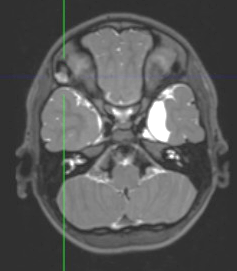

However, one year later, magnetic resonance imaging (MRI) showed a minimally enhancing cystic lesion (2.2 cm) with a similar radiological appearance, with T2 hyperintensity and no solid enhancement, located in the diploe of the greater wing of the right sphenoid. A “wait and see” strategy was decided, due to the risks associated with the removal of the lesion in this location, and no radiological changes in the MRI were reported up to date, 7 years later (Figure 4).

Figure 4: Non-treated myxoma in the sphenoid major wing. MRI control.